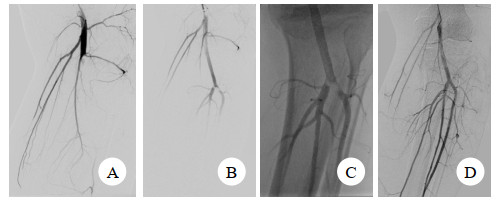

1.3 术后随访术后彩超或CTA,评估腘动脉通畅率及评估腘动脉覆膜支架是否发生变形/断裂。见图 1,图 2。

| 图 1 患者男,25岁 A:右膝关节脱位导致钝性腘动脉损伤;B:DSA显示腘动脉闭塞;C:植入肝素涂层的Viabahn覆膜支架开通腘动脉;D和E:术后8个月复查CTA提示右腘动脉显影良好、覆膜支架无变形 |